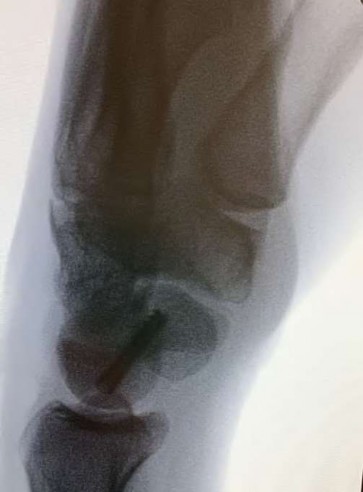

A 20-year-old park ranger trips and falls onto his right wrist with the wrist in extension and pronation. The local urgent care orders both radiographs and a CT, which you review and determine to be normal. The patient complains of ulnar-sided wrist pain. On exam, his tenderness is localized to the fovea. Ulnar deviation also causes him pain. There is no snapping sensation with wrist supination, flexion, and ulnar deviation. He otherwise has 5/5 strength to his first dorsal interosseous muscle with 4mm static two-point discrimination on the ulnar side of the 4th digit. Which of the following injuries is most likely responsible for his symptoms and exam?